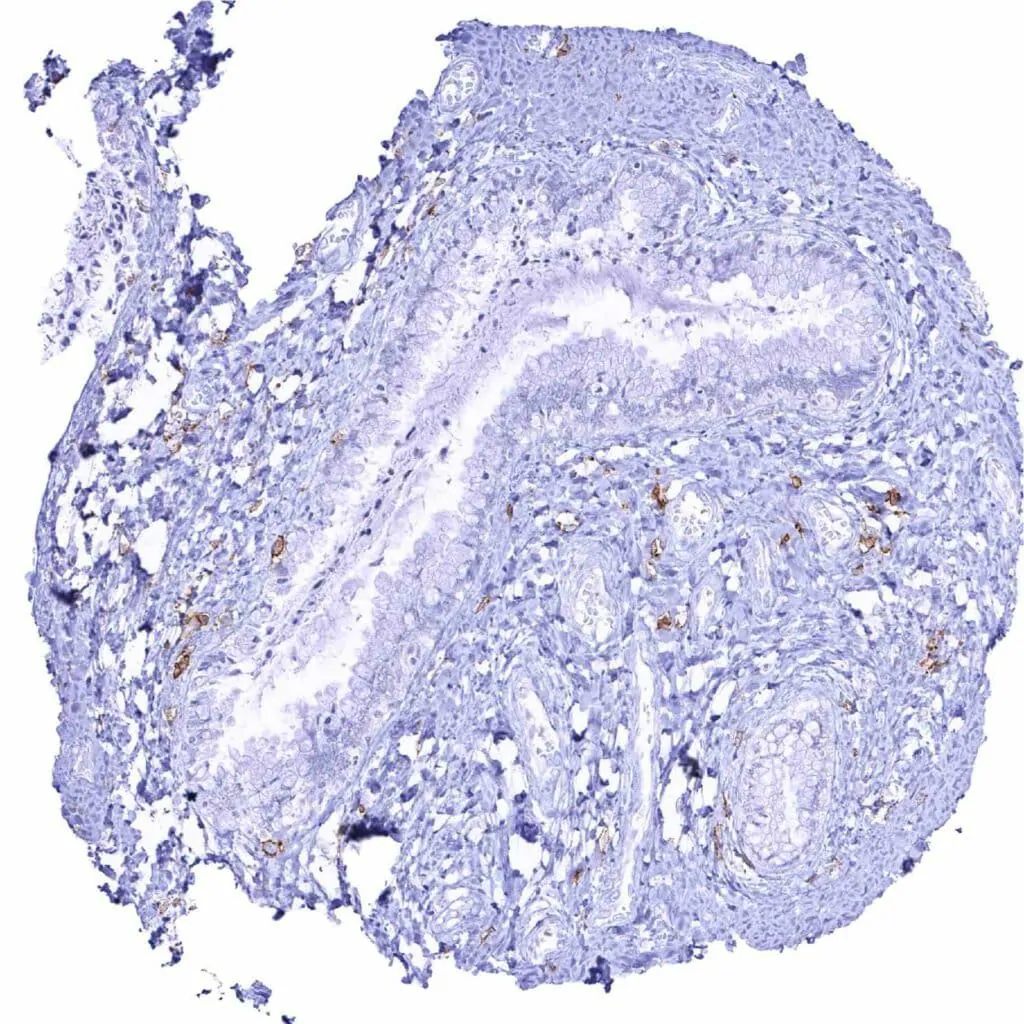

Appendix, muscular wall